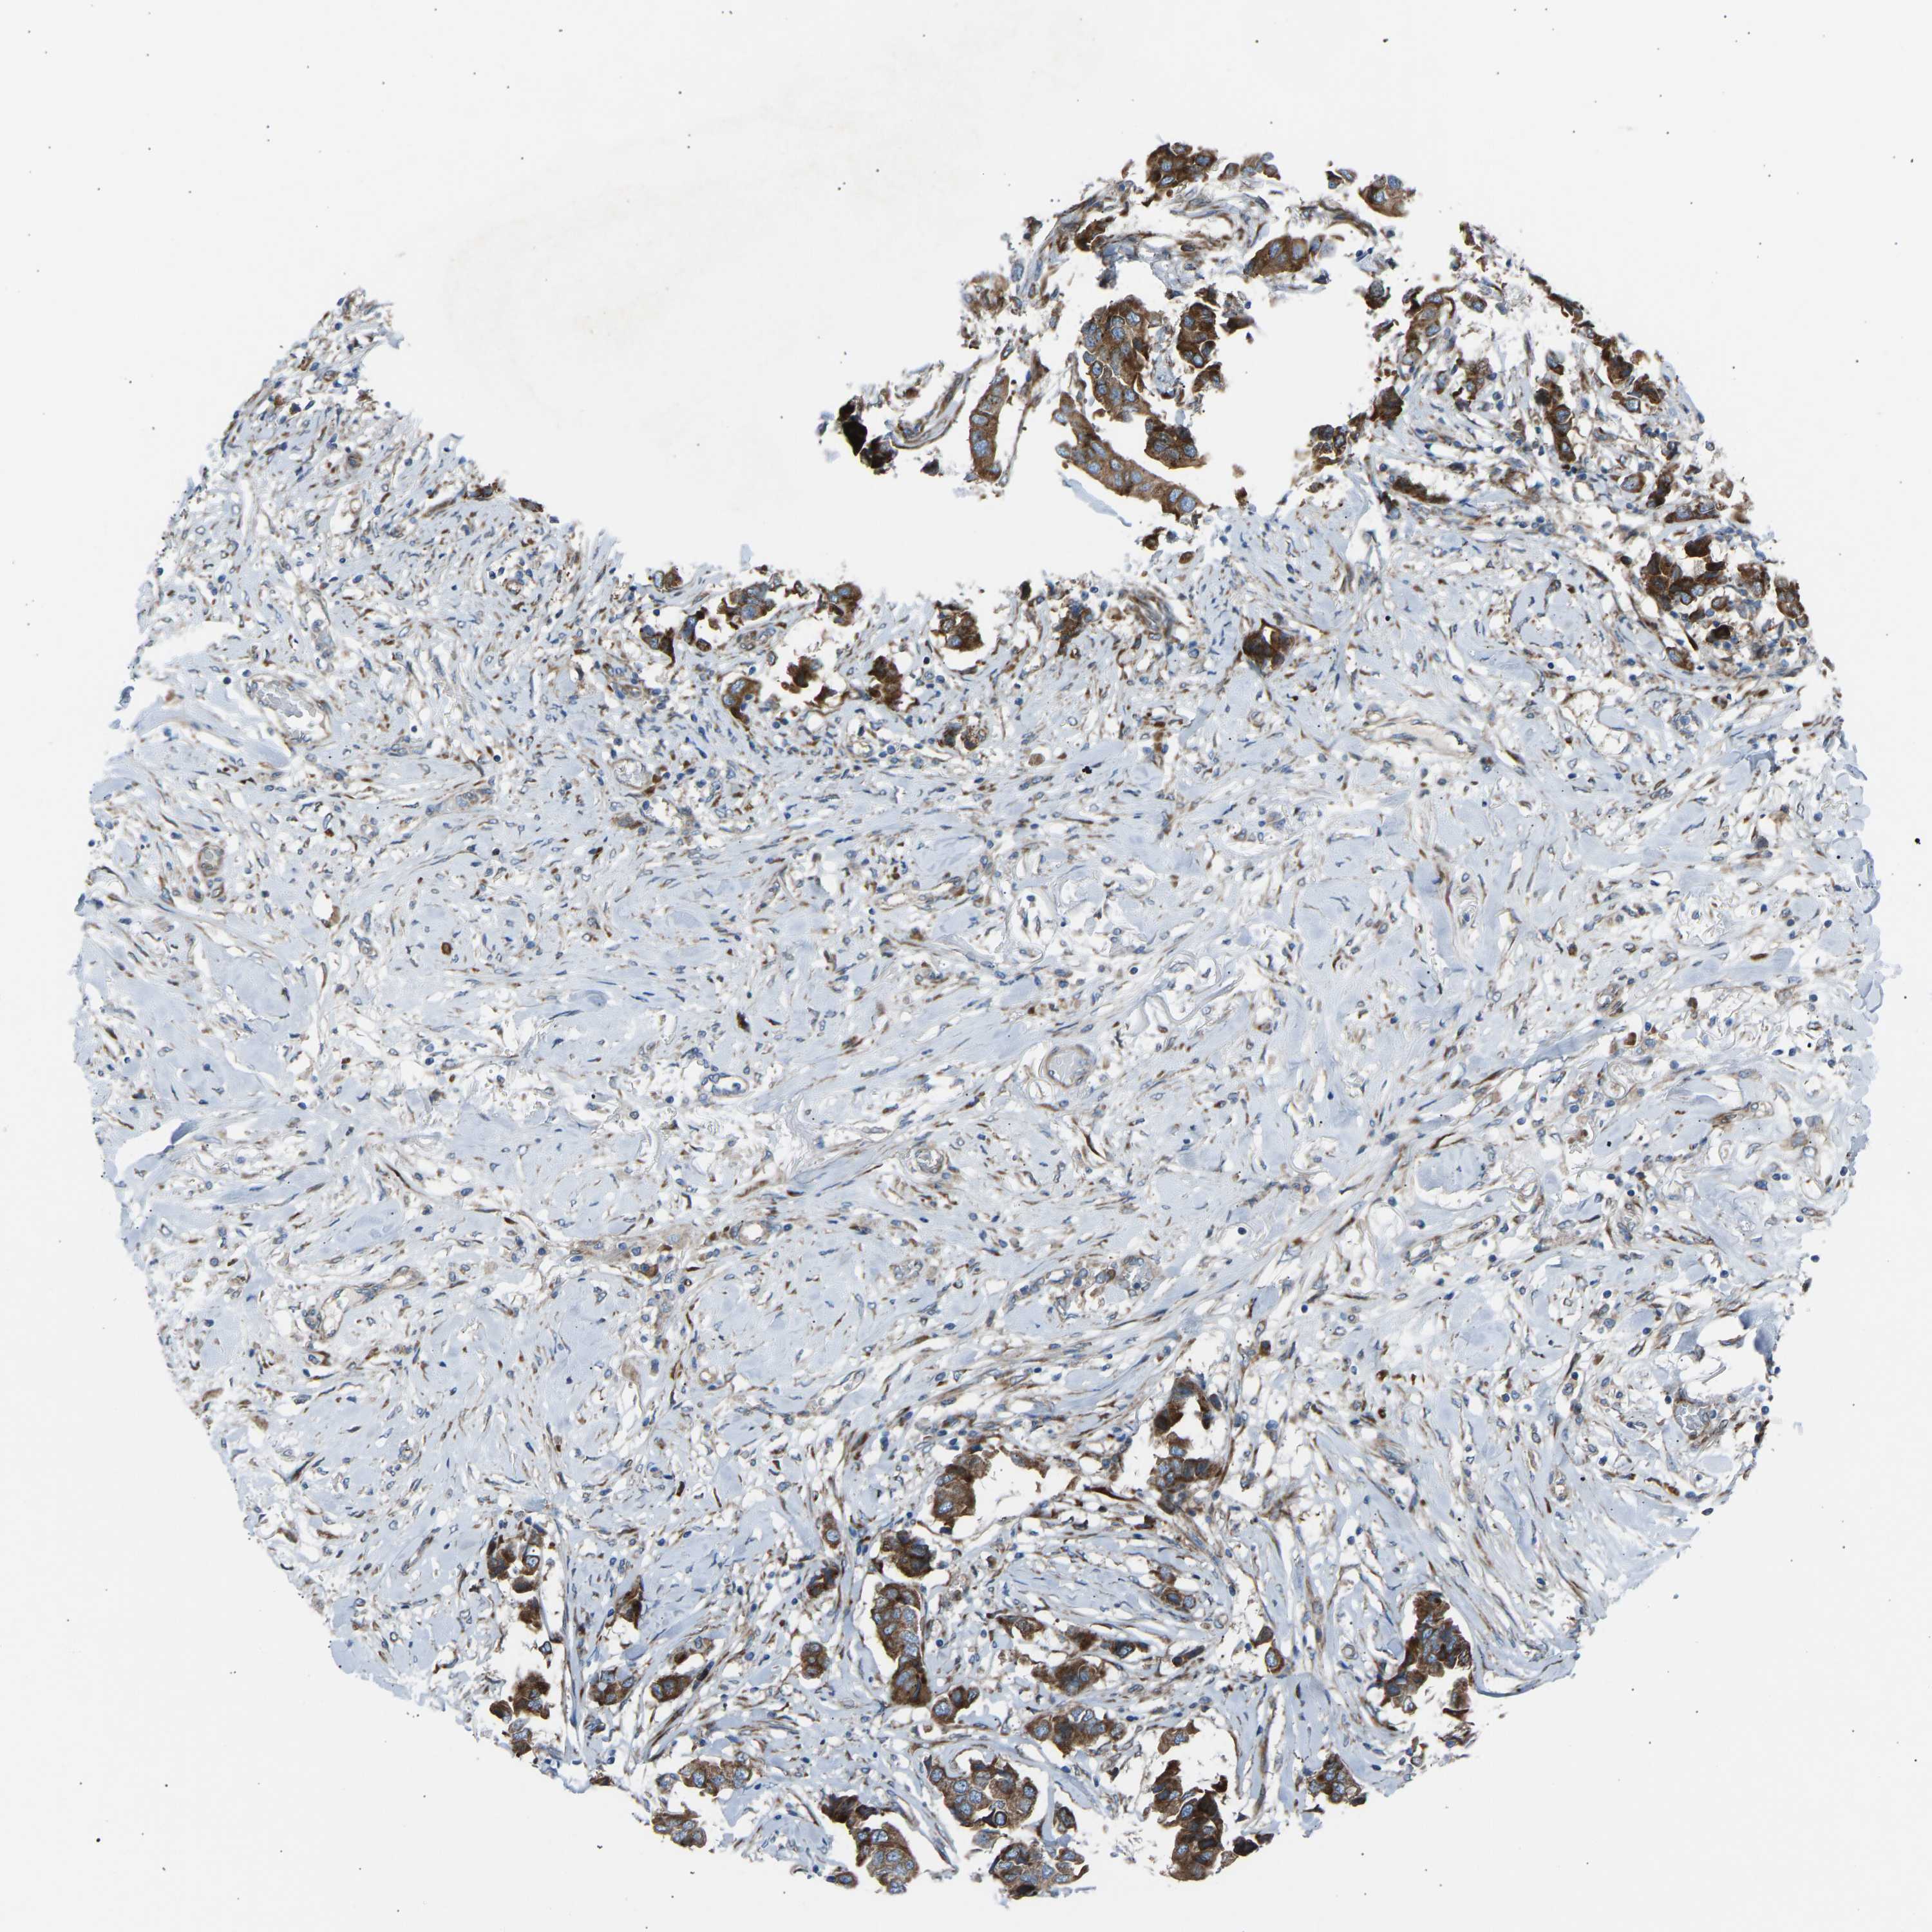

CANCER BREAST CANCER Show tissue menu

BRCA TCGA BRCA VALIDATION PROTEIN EXPRESSION

Breast cancer

Human cancer

Breast invasive carcinoma